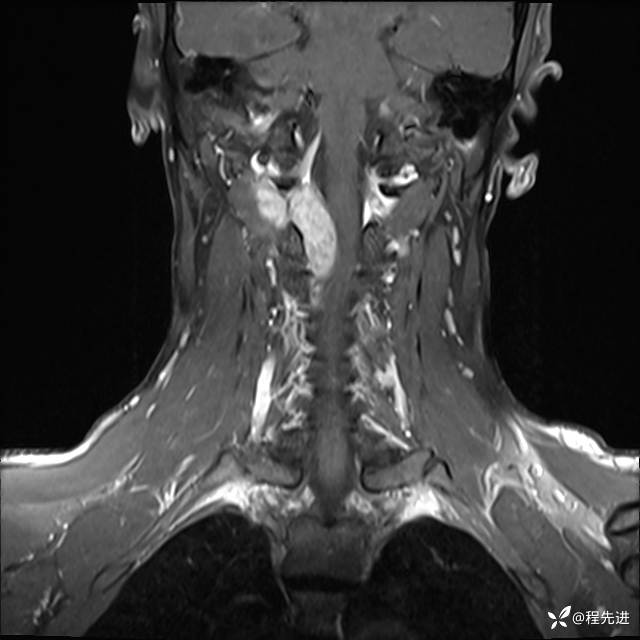

MRI平扫+增强:

T1增强: